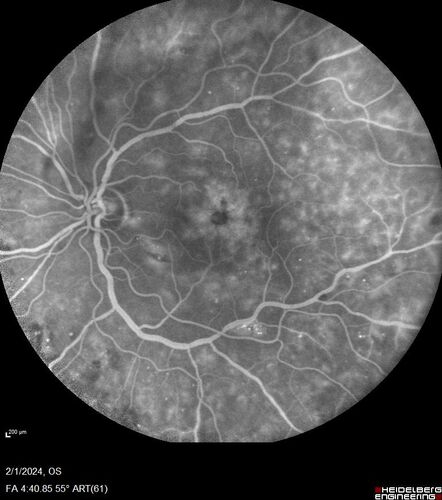

Chronic Myelogenous Leukemia and Diabetic Macular Edema

71 year old female with 3 months of vision loss and not feeling well.  She has been bruising on her legs.  Her vision was 20/100 in each eye with macular edema.  She was treated with Avastin and her CBC was checked.  She had a WBC of 267 thousand and was diagnosed with CML.